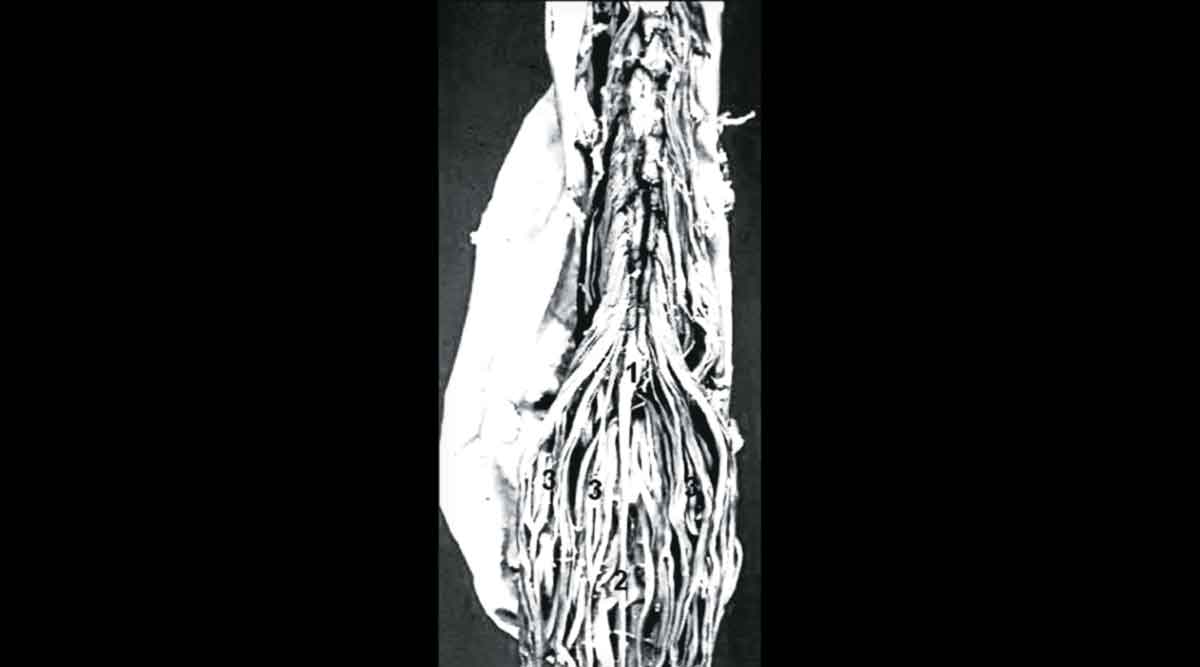

पाठीच्या कण्याच्या खालच्या म्हणजे कंबरेच्या भागात पाच मणके असतात आणि या मणक्यांच्या कॅनॉलमध्ये मज्जारज्जू नसतो हे त्याच्या लक्षात आलं. प्रौढ व्यक्तींमध्ये मज्जारज्जू कंबरेच्या मणक्याच्या वरच्या भागातच संपतो. (साधारण कंबरेच्या पहिल्या मणक्याच्या भागात). त्या खालच्या कॅनॉलमध्ये मजारज्जू नसला, तरी त्यापासून निघणाऱ्या नसा खचाखच भरलेल्या असतात. दोनही नितंबांकडे, जननेंद्रियांकडे, मांडय़ा, पोटऱ्या, पावलं यांकडे जाणाऱ्या नसा इथल्या कॅनॉलमध्ये दाटीवाटीने भरलेल्या असतात.

या भागाची संरचना अभ्यासताना तो लिहितो – ‘ज्याप्रमाणे घोडय़ाची शेपटी त्याच्या पाठीच्या मागच्या टोकापासून सुरू होऊन अनेक जाडसर केसांमध्ये विभागते, त्याप्रमाणेच मज्जारज्जू संपून त्यापासून जाड नसांचा पुंजका बाहेर आलेला दिसतो. विच्छेदनात कंबरेच्या मणक्याचा कॅनॉल उघडल्यावर ही रचना अगदी तंतोतंत ‘घोडय़ाच्या शेपटी’सारखी दिसते..’ म्हणून त्याने या नसांच्या पुंजक्याला ‘कॉडा इक्वायना’.. म्हणजेच ‘घोडय़ाची शेपटी’ असं नाव दिलं. कॉडा म्हणजे शेपटी आणि इक्वायना म्हणजे घोडय़ाची. हे नाव १६०५ साली दिलं गेलं असलं तरी आजही न्यूरोसर्जरीमध्ये जसंच्या तसं प्रचलित आहे.